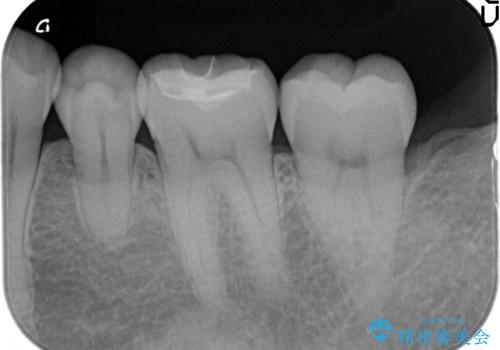

- 左下6番目の歯がしみるので診て欲しいといらっしゃった方の症例です。

古い樹脂及び虫歯を除去後、セラミックインレーによる修復を行いました。